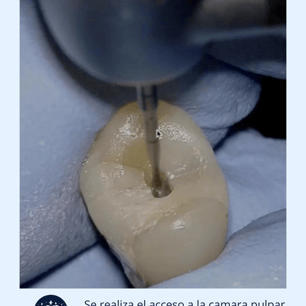

Acceso al Conducto: Se hace una apertura en la corona del diente para acceder al conducto radicular.